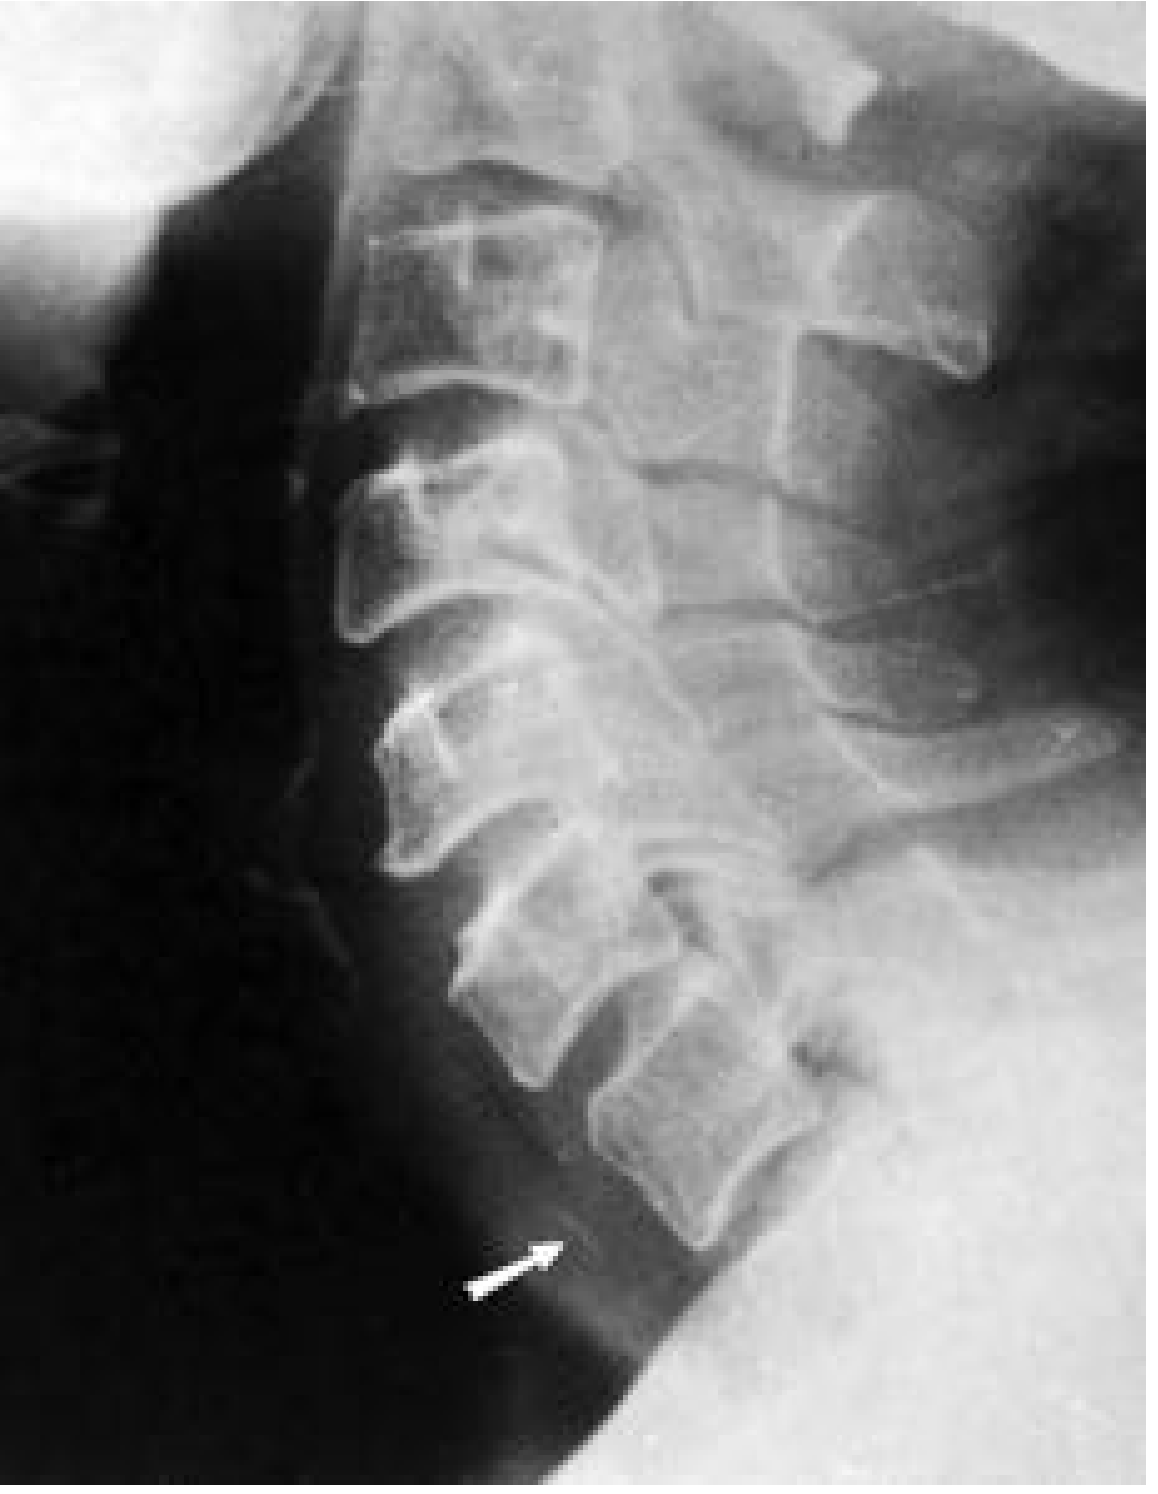

Lateral neck X-ray: chicken bone at pharyngoesophageal junction

Lateral soft tissue X-ray shows chicken bone (arrow) at the pharyngoesophageal junction. — Cummings Otolaryngology